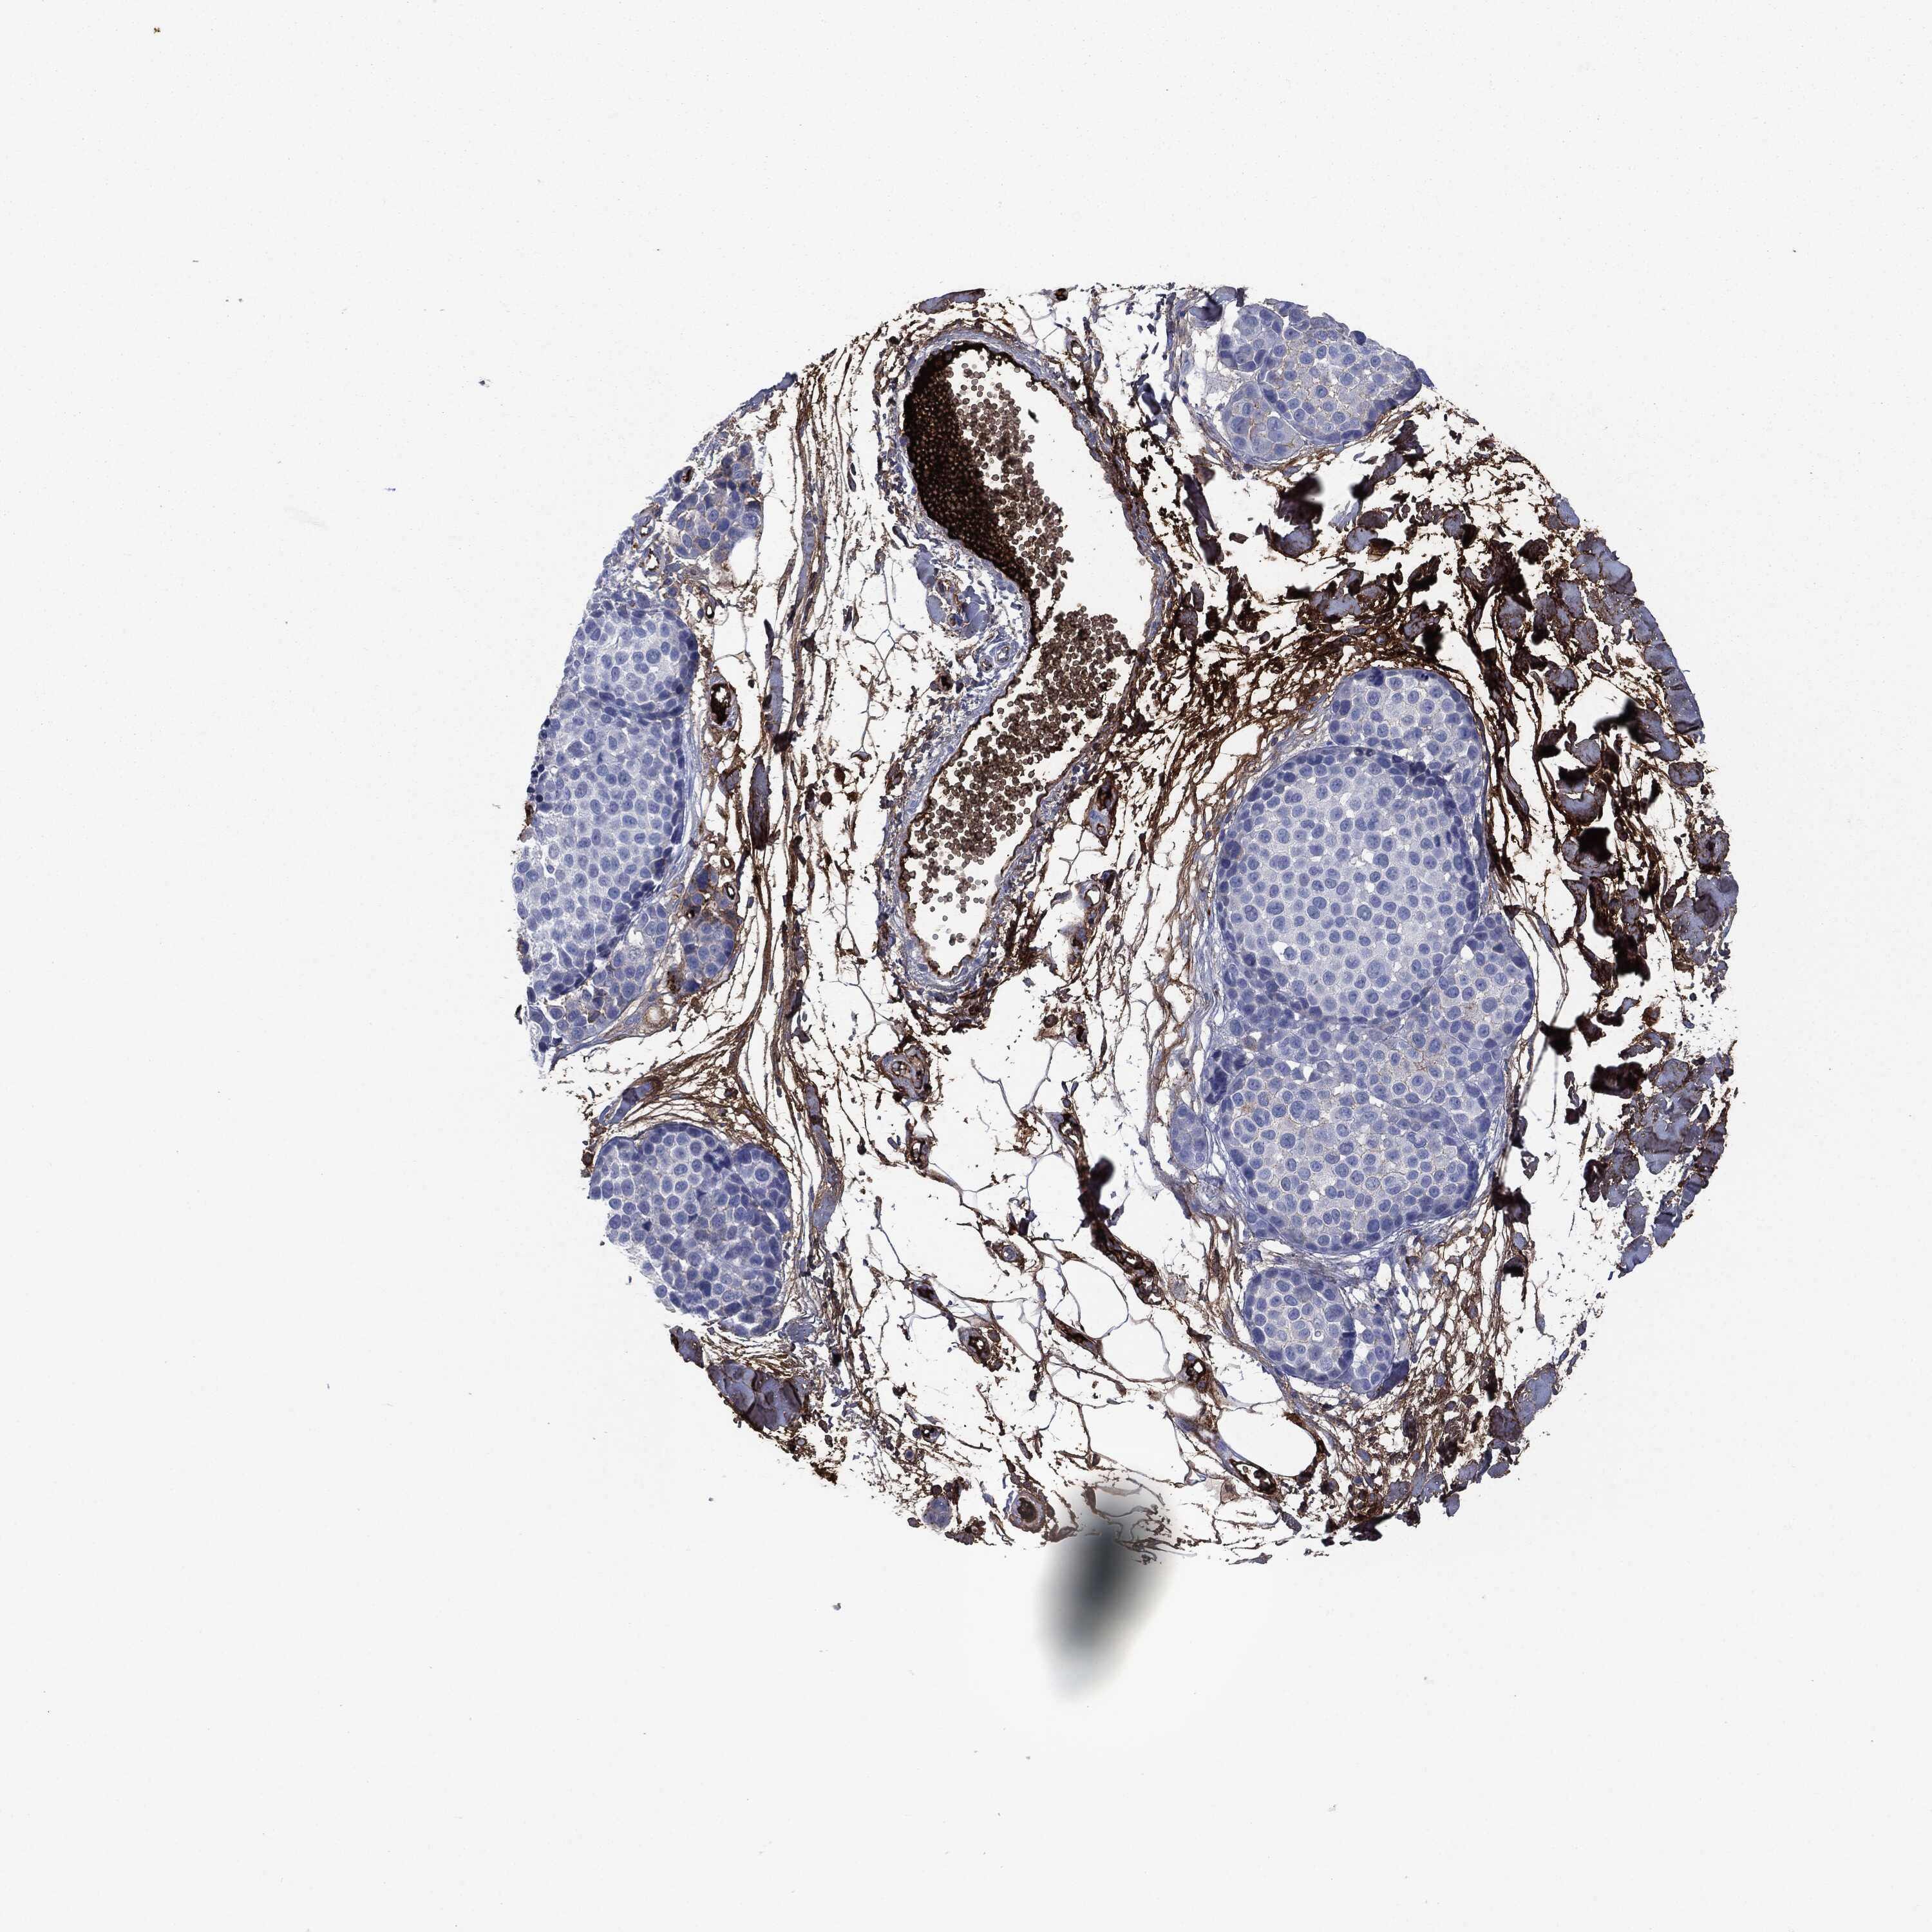

MELANOMA - Protein expressioni

A mouse-over function shows sample information and annotation data. Click on an image to view it in a full screen mode. Samples can be filtered based on level of antibody staining by selecting one or several of the following categories: high, medium, low and not detected. The assay and annotation is described here.

Note that samples used for immunohistochemistry by the Human Protein Atlas do not correspond to samples in the TCGA dataset.

Antibody stainingi

Antibody staining in the annotated cell types in the current human tissue is reported as not detected, low, medium, or high, based on conventional immunohistochemistry profiling in selected tissues. This score is based on the combination of the staining intensity and fraction of stained cells.

Each image is clickable and will lead to virtual microscopy that enables deeper exploration of all samples and also displays staining intensity scores, fraction scores and subcellular localization as well as patient and tissue information for each sample.

HPA049793

CAB016070

CAB080297

CAB080298

CAB080299

Staining

High

Medium

Low

Not detected

Intensity

Strong

Moderate

Weak

Negative

Quantity

>75%

75%-25%

<25%

None

Location

Nuclear

Cytoplasmic/membranous

Cytoplasmic/membranous,nuclear

Malignant melanoma, NOS

Malignant melanoma, Metastatic site